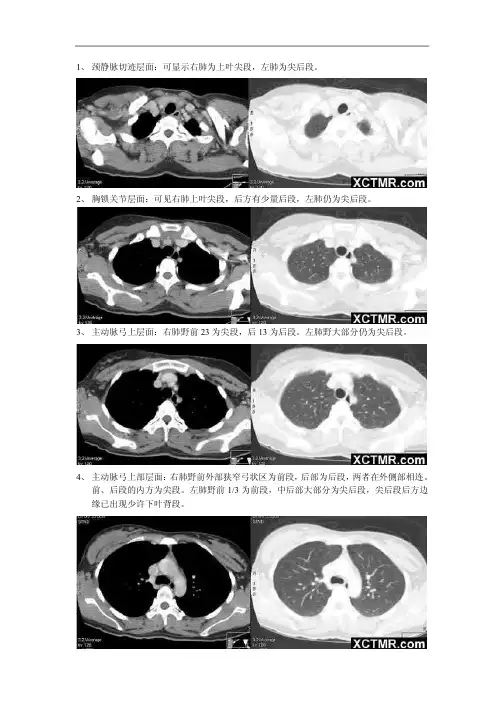

正常胸部肺窗CT解剖(1)气管分叉层面右眄功请祈干右种上叶可绘支气曽占上叶肺林赣后交右上叶后議复气令石比打赍气管左干y详左上斜諾E饪支F善丘肺璃H右上叶支气管层面左主支气管中段层面左上叶固有段与舌段支气管分叉层面正常胸部肺窗CT解剖(2)右殊上阳右齋T叶A-tHk右中叶支气管开口层面显示双侧斜裂层面右脑下叶若満上肝A-M H■+左歸下科显示各肺叶层面下肺层面正常胸部纵隔窗CT解剖(1)右皆飞幼恋咅*1训衬K胸锁关节层面(平扫)右辿訣尬腺右虫站的肤右硕脅F肚脳禰11肿咼音皆Gi*^k胸锁关节层面(增强)知忏主动脉弓上层面(平扫)左头欝醉轴左抽忌砧忏王號告F话尿主动脉弓上层面(平扫)正常胸部纵隔窗CT解剖(2)土罚辭弓上剋一巳曲气餐輔绘歸肚冶闻Aft主动脉弓层面(平扫)片主撷*i工力气笛石主直气餐气管分叉层面(平扫)Array气管分叉层面(增强)r府卿中闾段支円普肺动脉干与右肺动脉层面(平扫)弭动孝干左肺曰矗蘇&誌动忏奇謎栋正常胸部纵隔窗CT解剖(3)右,心卫:肺讪业吓幅霑古壬it站瞄血帅上卩帥左岭卜阳姑左心房层面(平扫)右卍耳主动珊強右讪工絆脉在"胪朝球干帳那左冠状衲凍片心耳左心房层面(增强)ti室证出壇王昭躲QS-L'ffi左、右心房层面(增强)左心當四腔心层面(平扫)正常胸部纵隔窗CT解剖(4)心也期耶垫“J®下呼静詠心室层面(平扫)。

【每日一图】胸部正常CT解剖胸部正常CT横断面增强扫描:肺窗气管分叉层面1.右肺上叶前段;2.上腔静脉;3.右肺上叶后段;4.右肺斜裂;5.左肺上叶前段;6.气管分叉;7.左肺上叶尖后段;8.左肺斜裂左右主支气管层面1.右主支气管;2.右侧肺门;3.右肺上叶前段支气管;4.右肺下叶背段;5.左主支气管;6.左肺上叶前段支气管;7.左肺上叶尖后段支气管;8.左肺下叶背段右中间段支气管层面1.胸骨;2.右肺上叶;3.右中间段支气管;4.右肺叶间裂;5.右肺下叶背段;6.左肺下叶支气管;7.左肺上叶前段;8.左肺上叶尖后段支气管;9.左肺斜裂;10.左肺下叶背段左右支气管基底干层面1.右肺上叶前段;2.右肺中叶内侧段支气管3. 右肺中叶外侧段支气管;4.右肺下叶支气管基底干;5.右肺下叶背段;6.左肺上叶前段;7.左肺上叶上舌段;8.左上肺静脉;9.左肺下叶背段右下肺静脉层面1.右肺中叶;2.右上肺静脉;3.右下肺静脉;4.左肺上叶舌段;5.左下肺前内基底段支气管;6.左下肺后基底干支气管;7.左下肺静脉各基底段支气管层面1.右肺中叶内侧段;2.右肺中叶外侧段;3.右肺下叶前基底段;4.右肺下叶基底干;5.右肺下叶后基底段;6.左肺舌段;7.左肺下叶内、前基底段支气管;8.左肺下叶外侧基底段支气管;9.左肺下叶后基底段支气管资料来源:《医学影像学读片诊断图谱——胸部分册》主编邹煜高莉。